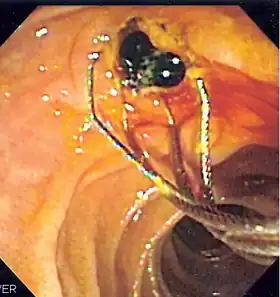

![]() Duodenoscopic image of two black pigment stones extracted from common bile duct after sphincterotomy | |

- Extraction of gallstones or other biliary debris[4]

When needed, the sphincters of the ampulla and bile ducts can be enlarged by a cut (sphincterotomy) with an electrified wire called a sphincterotome for access into either so that gallstones may be removed or other therapy performed.[10]